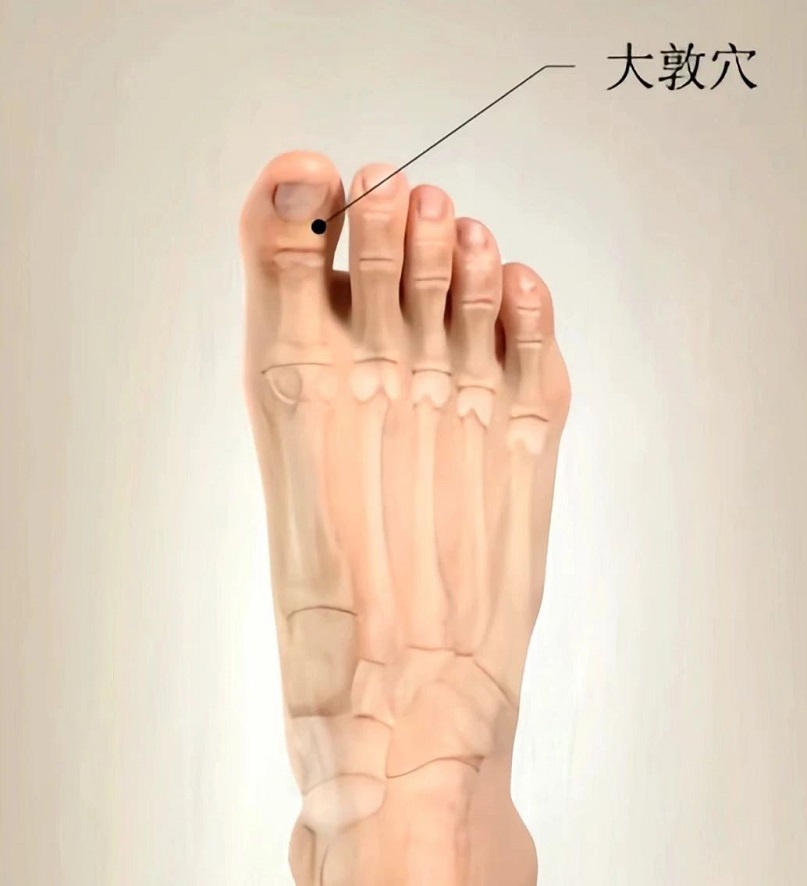

合歡花,解郁安神、可改善心神不安、胸悶、視物不清、失眠等情況,可取適量泡茶飲用。(參考《藥典》)大敦穴是肝經的第一個穴位,它在大腳趾內側的趾甲縫旁邊。此穴可以按摩,也可以艾灸,能達到清肝明目之功效,可使頭腦清晰、神清氣爽。行間穴在大腳趾和二腳趾縫上,是一個火穴。肝屬木,木生火,如果肝火太旺,就要瀉其心火,而行間穴就是一個瀉心火的穴位。春天肝火盛,會出現牙痛、腮幫子腫、口腔潰瘍、鼻出血、舌尖長皰等癥,多揉行間穴能緩解上述癥狀。足三里穴在外膝眼下3寸(即四橫指),距脛骨前嵴1橫指,當脛骨前肌上。取穴時,由外膝眼向下量4橫指,在腓骨與脛骨之間,由脛骨旁量1橫指處即是穴。足三里穴是足陽明胃經的主要穴位之一,具有調理脾胃、補肝益氣、通經活絡、疏風化濕、扶正祛邪之功能。(內容參考廣東中醫藥公號)